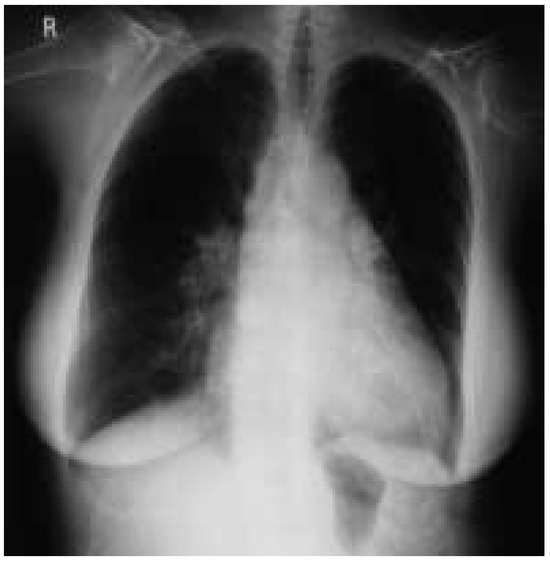

Case description A 70-year-old former athlete complained about a twenty-year history of paroxysmal atrial fibrillation with onset at rest and during the night, which became persistent in the last three years [...]